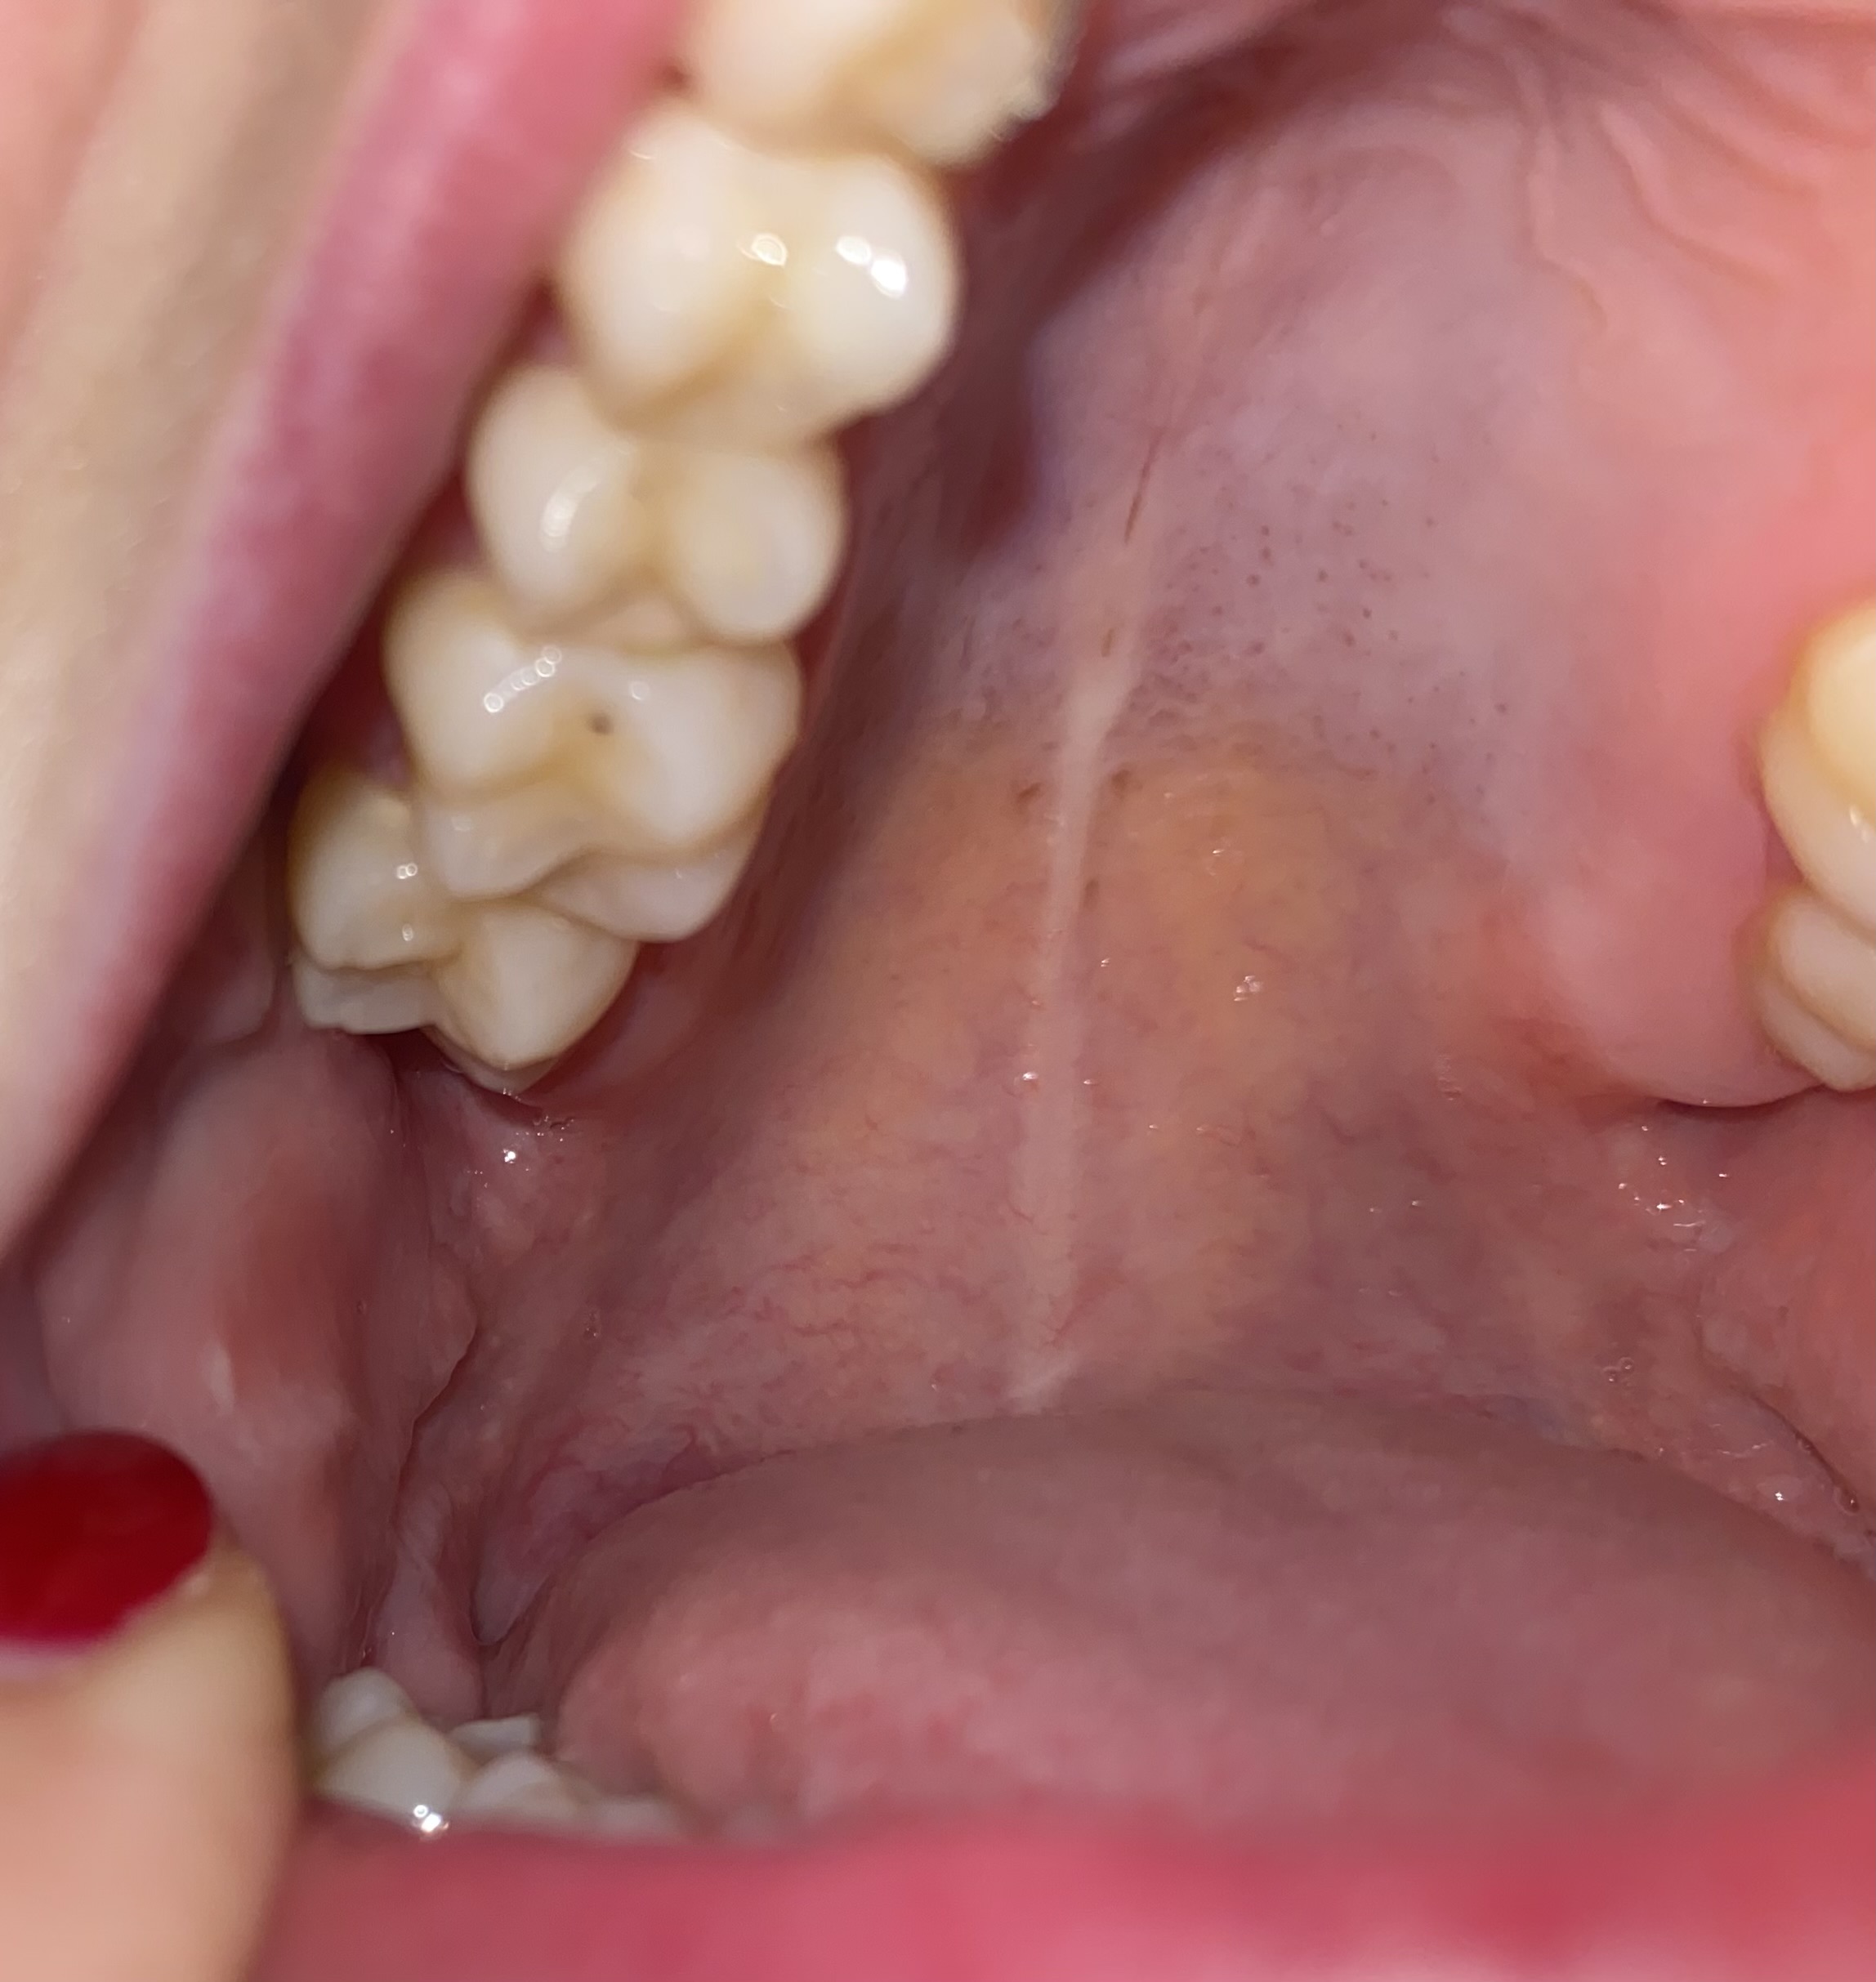

Twee weken geleden ben ik bij de tandarts geweest. Nu keek ik vanmiddag in de spiegel en zag ik een zwart stipje op mijn kies (zie foto). Is dit een gaatje? Ik heb verder geen last maar het viel mij ineens op.

Foto is niet duidelijk. Niet elk stipje is een gaatjedie behandeld moet worden. Maar zover ik dit kan beoordelen is dat niet nodig. Maar voor de zekerheid zou ik een recente x-foto moeten zien.